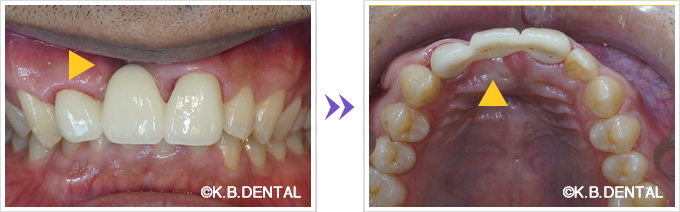

上顎外側骨隆起 症例1

咬合の応力は上顎の場合、必ずしも口蓋正中に集中するわけではありません。

歯列や歯牙の傾斜の角度により外側に分散することがあります。

その場合、上下とも外側に大きな骨隆起を生じます。

これが大きくなりすぎると食物残渣の停滞を引き起こし口腔内の不快感、口腔衛生状態の悪化につながります。

治療は外科的に除去することが第一選択肢となります。

上顎外側骨隆起 症例2(上顎の頬側にできた骨隆起)

笑った時にゴボ口となりやすく、隆起した部分に食物残渣などが生じやすいケースです。静脈麻酔で約1時間半程度要します。